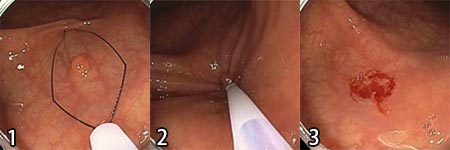

コールドポリペクトミー(Cold Polypectomy)

輪っか状の鉗子を、ポリープの根元にかけ、締め付け、そのまま切除する方法です。通電はしません。主に10mm未満の平坦な形態のポリープが対象となります。後述する通電する方法と異なり、後出血や穿孔等の偶発症の発現頻度が少ない点がメリットです。

- ポリープにコールドポリペクトミー専用の鉗子をかけます。

- 鉗子のワイヤーを締め上げてポリープを切除します。

- 切除部に少量の血液が付着し、これが固まって(血餅)、自然止血が促されます。